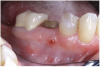

Figure 3 Clinical view of site No. 12 demonstrating pus upon palpation. Pus can be different colors. Not all infected sites manifest pus. (Photograph courtesy of Dr. John Cavallaro.)

Figure 3

Suppuration is a cardinal sign of an infection, yet it may not be present. Pus is usually a thick viscous fluid that is often created in response to an infection. As the neutrophils die, they are destroyed by macrophages, thereby forming pus. Pus is usually white or yellow, but it can be red, green, or blue (Figure 3 and Figure 4).18 White and yellow pus typically reflect an infection with Streptococcus pyogenes or Staphylococous aureus.19 A red discharge reflects blood mixing with the pus. If the pus is green, it is due to incorporation of myleperoxidase, which is produced by neutrophils.19 A clear fluid (serum) reflects healing and is not considered a sign of an infection.19